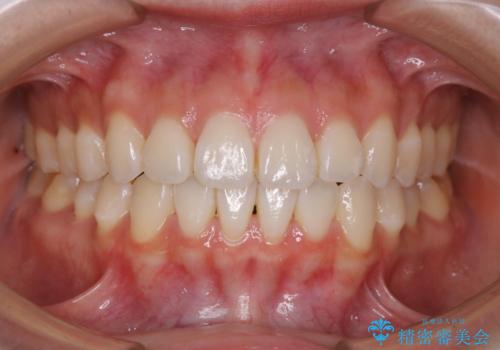

前歯で噛めない:オープンバイト(開咬)を非抜歯インビザラインで治療

- 1年3ヶ月

オープンバイトの方への治療は、通常抜歯を行いワイヤーによる矯正治療を行うことが多いですが、今回はインビザラインの特性を生かし、非抜歯にて綺麗な歯並びを作ることが出来ました。